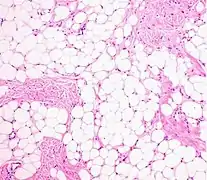

Histopathology of a lipoma: The mass is composed of lobules of mature white adipose tissue divided by fibrous septa containing thin-walled capillary-sized vessels.[25] H&E stain.